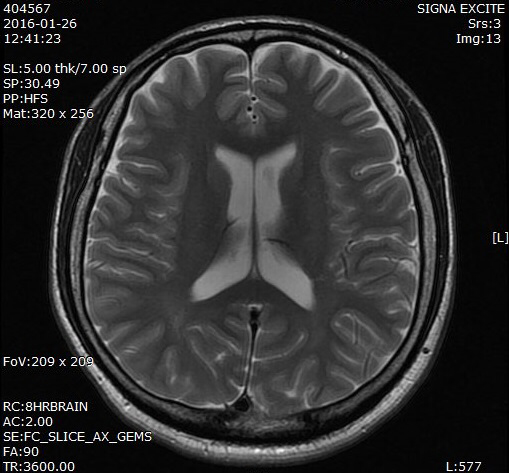

나는 신경과 의사다. 우선 신경과는 뇌, 신경, 척수, 근육 등에 관련된 의학이다. 다루는 질환 들로는 뇌졸중(뇌경색, 뇌출혈 등), 뇌전증 (과거 '간질'이라고 불림), 두통, 어지럼증, 손발 저림, 수면장애, 운동장애 (파킨슨병, 수전증 등) 등 이 있다. 그중 외래에서 가장 흔하게 보게 되는 질환 중 하나가 두통이다. 전 세계 인구 중 90% 이상이 일생을 살면서 한번 이상 경험하는 것이 두통이다. 그만큼 흔한 증상이자 일차진료를 찾게 될 때 가장 많이 호소하는 것 중 하나이다. 두통환자분들을 볼 때 가장 많이 받게 되는 질문이 하나가 있다. 이는 "혹시 내 머리에 무슨 문제나 병이 있는 것은 아닐까?"이다. 두통의 원인은 약 300여 가지가 있는데, 사실 뇌종양이나 뇌졸중 등과 같이 뇌 자체에 문제가 발생해서 두통이 생기는 경우는 그리 많지 않다. 그리고 실제로 드물다.

두통은 크게 일차성 두통과 이차성 두통으로 나뉜다. 일차성 두통이란 혈액검사나 뇌 촬영 등으로 아무리 검사해도 확인되지 않는 두통이다. 그럼 어떻게 진단하느냐? 바로 문진 (History Taking)을 통해서 진단한다. 문진이란 두통이 언제, 어떻게, 어떤 양상으로 생겼는지, 동반 증상은 없는지? 기저 질환 등은 없는지? 등을 물어보고 그러한 증상들이 특정 두통의 진단 기준에 맞으면 이를 진단하게 되는 것이다. 대부분의 사람들이 겪고 있는 두통이 바로 이와 같은 일차성 두통이다. 일차성 두통의 예로는 "긴장성 두통", "편두통", "근막동통 증후군" 등이 있다.

그럼 이차성 두통이란 어떤 것일까? 이차성 두통은 여러분들이 걱정하고 두려워하는 뇌에 문제가 생기는 경우라 할 수 있다. 그 외 뇌에는 문제가 없어도 기타 다른 질환 즉 안과적(녹내장, 연부조직 감염 등), 이비인후과적 (축농증, 비염, 중이염, 이하선염 등) 혹은 치과적 문제 (턱관절염, 부정교합 등) 혹은 감염(뇌수막염, 감기, 독감, 등) 등의 뚜렷한 원인에 의해 발생하는 두통을 이차성 두통이라고 일컫는다. 즉 두통을 일으키는 뚜렷한 신체적 그리고 기질적 원인이 있는 두통을 이차성 두통이라고 말할 수 있다.

여기서 필자는 놀라운 사실을 하나 말씀드리겠다. 바로 '뇌' 자체는 통증을 느끼지 못한다 는 것이다. 이는 마치 우리가 미용실에서 머리를 가위로 자르거나 열 고문을 시켜도 통증을 느끼지 못하고, 손톱을 자를 때 통증을 느끼지 못하는 것과 비슷하다. 즉 우리 몸에는 통증을 느끼는 구조물과 그렇지 않은 구조물이 있다. 다른 한 예로 뼈가 부러지는 사고가 발생하면, 극도의 말로 표현하기 힘든 고통을 받는다. 사실 뼈 자체는 통증을 지각하지 못한다. 그럼 왜 아프냐? 바로 뼈를 싸고 있는 골막, 주위 인대 및 기타 주변 조직에서 통각을 느껴 통증을 느낀다. 여하간 통증을 느끼는 구조물과 그렇지 않은 신체 조직이 있는데 바로 우리 "뇌"는 통증을 느끼는 신체기관이 아니라는 것이다.